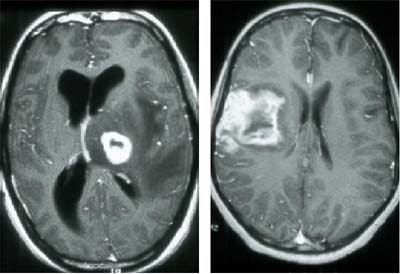

In early HIV disease there is often perivenular lymphocytic infiltration, particularly at the gray-white matter interface, Corr said. The infiltration is often seen in MRI as patches in the subcortical white matter and in the basal ganglia.

| Perivenular infiltration in the brain of an HIV patient. Images courtesy of Dr. Peter Corr. |